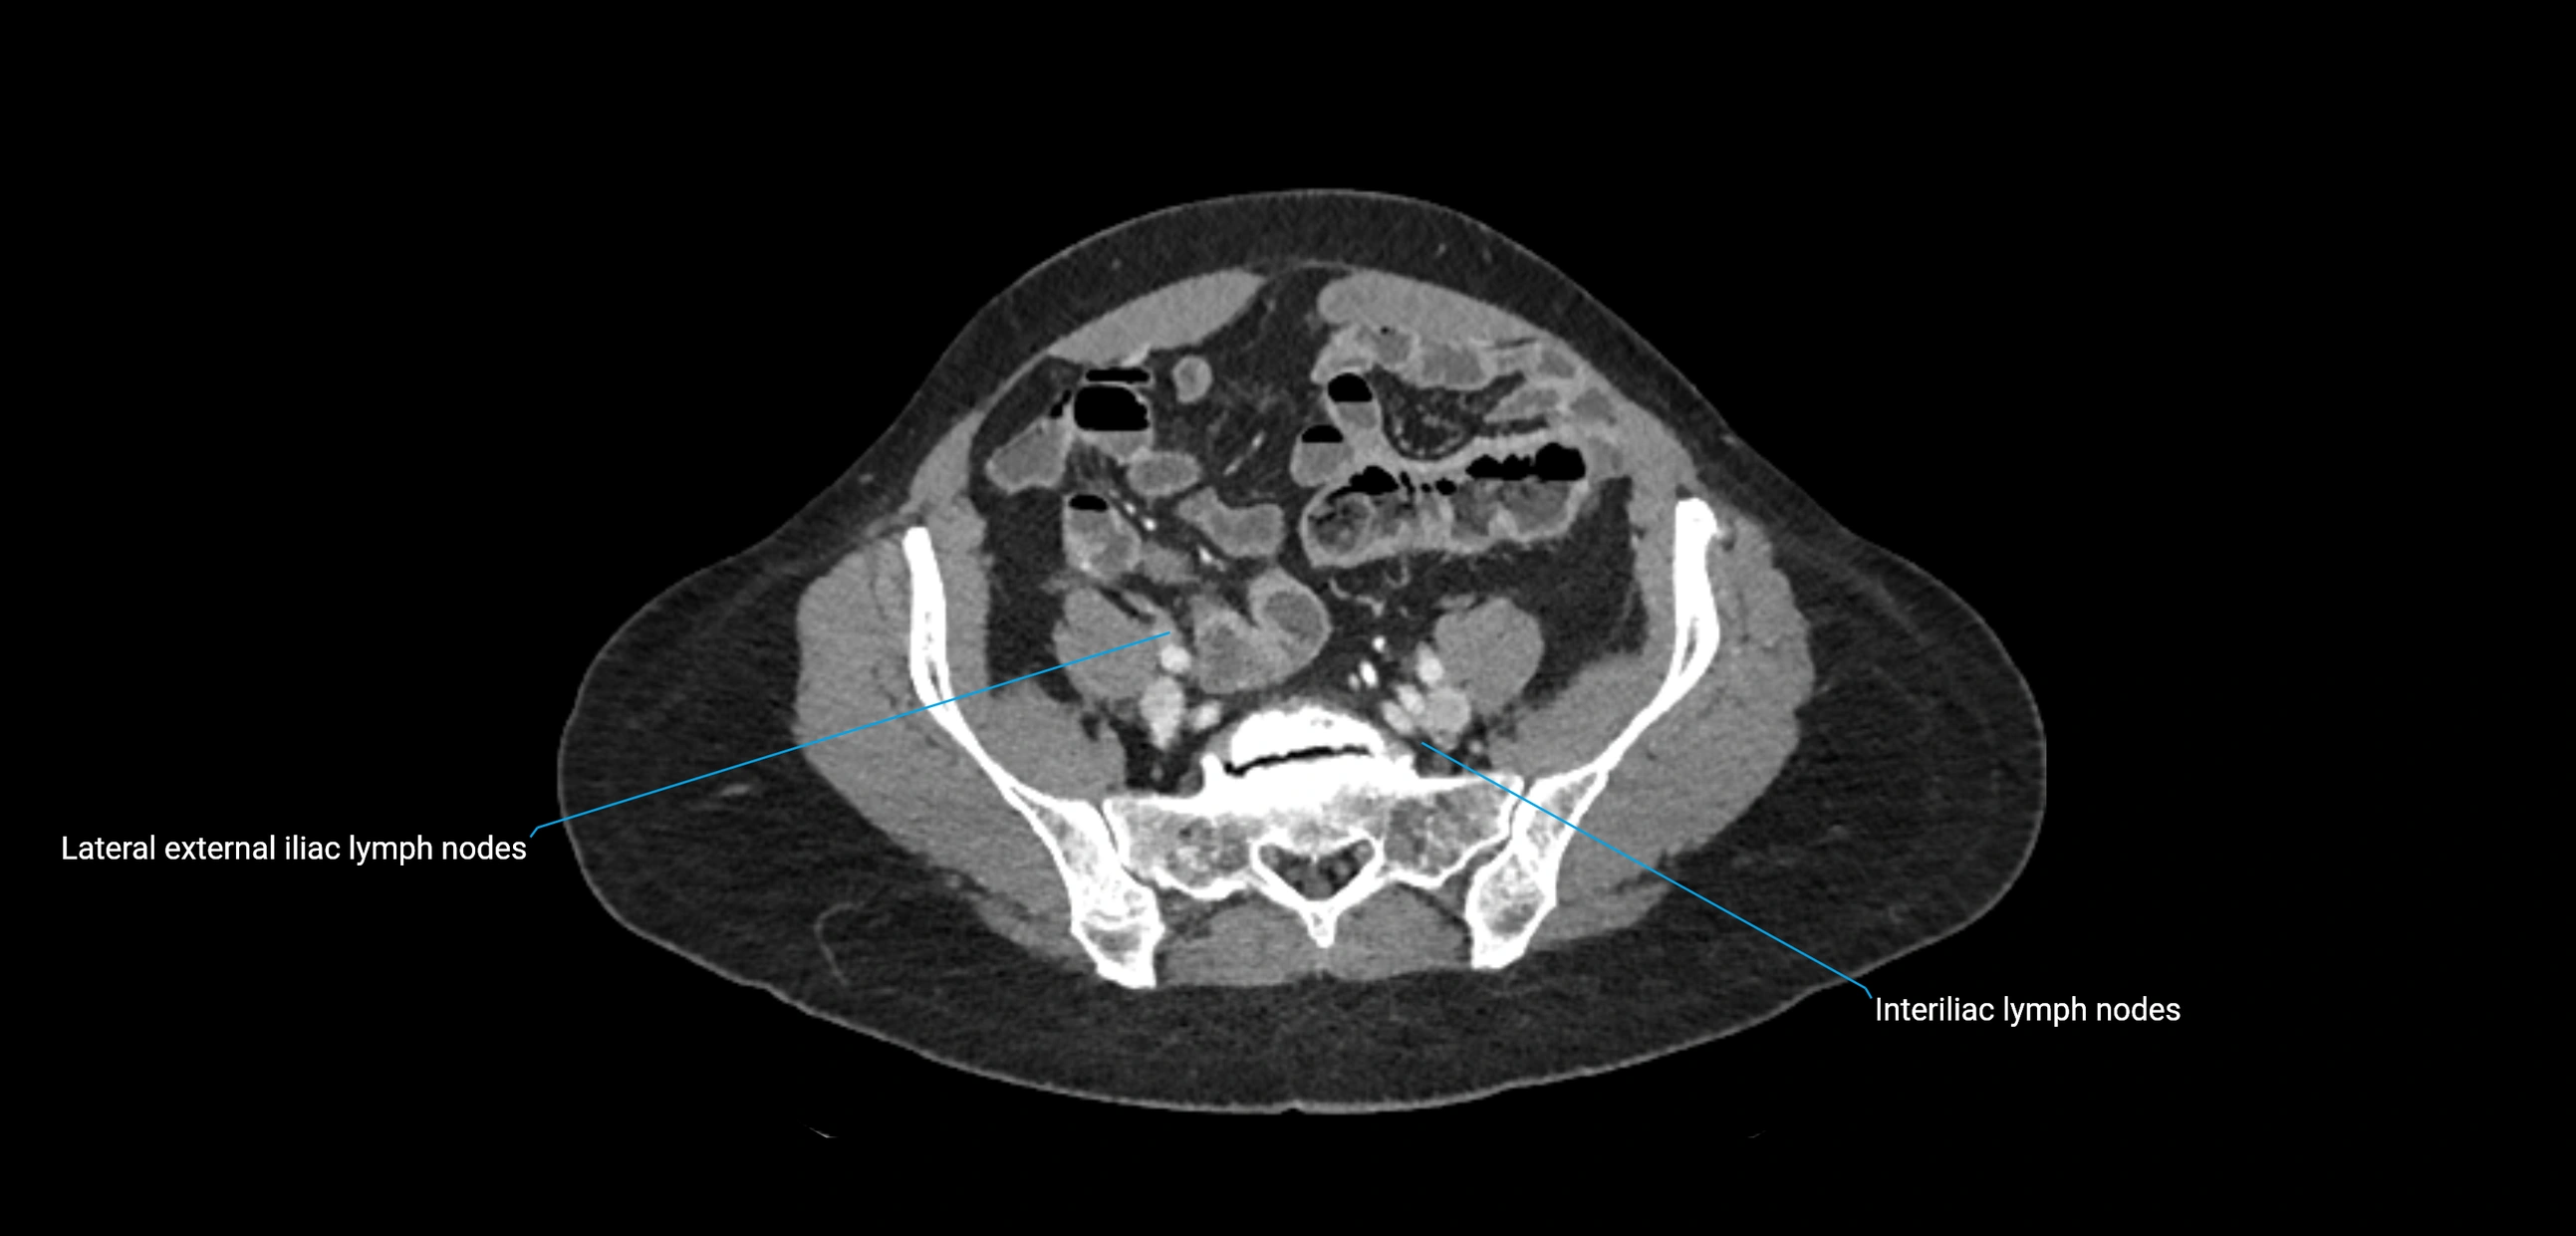

CT image

image